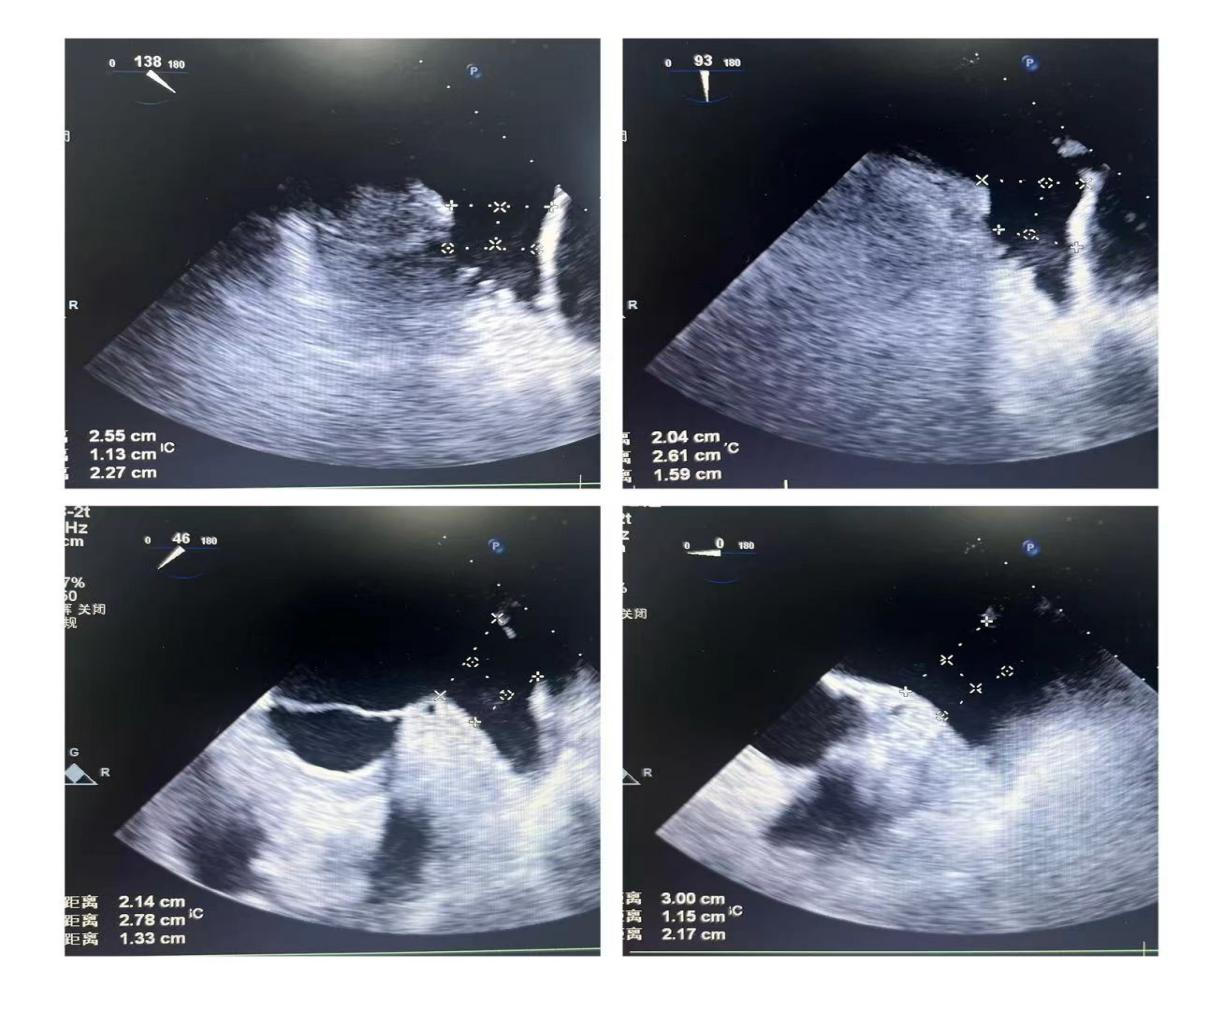

潘教授通过食道超声从4个不同的角度来观察患者左心耳的形态情况,显示心耳为反鸡翅型,位置较低,锚定区为23mm,封堵区为26mm。术者结合多年的临床经验,最终选用型号为LT-LAA-2632的LAmbre™左心耳封堵器对患者进行封堵。

▲(图:通过超声观察进行穿刺)

在食道超声引导下进行房间隔穿刺,由于心耳为反鸡翅型,穿刺位点需靠下靠前,潘教授先在90度双腔切面将定位靠下,再在45度主动脉短轴切面将定位靠前。穿刺成功后上导丝交换彩神在线网信彩票-彩神通免费版下载-彩神8争霸vlll-彩神购彩购彩大厅-彩神软件陆立根免费版-彩神ll争霸3-彩神ll彩神8-彩神ll争霸彩票-拼搏在线彩神网网页版LAnavi™分段控弯导引系统送至心耳口部,经过A、B双弯的调整使得鞘管轴向与心耳同轴,获得理想封堵位置。然后推送钢缆释放出固定盘,锚定后退鞘释放出封堵盘。超声下观察贴合良好,无明显残余分流,牵拉测试稳定,即释放左心耳封堵器。释放后再次通过超声各个角度进行验证,封堵结果完美有效,整个过程一气呵成,手术取得了极大的成功。